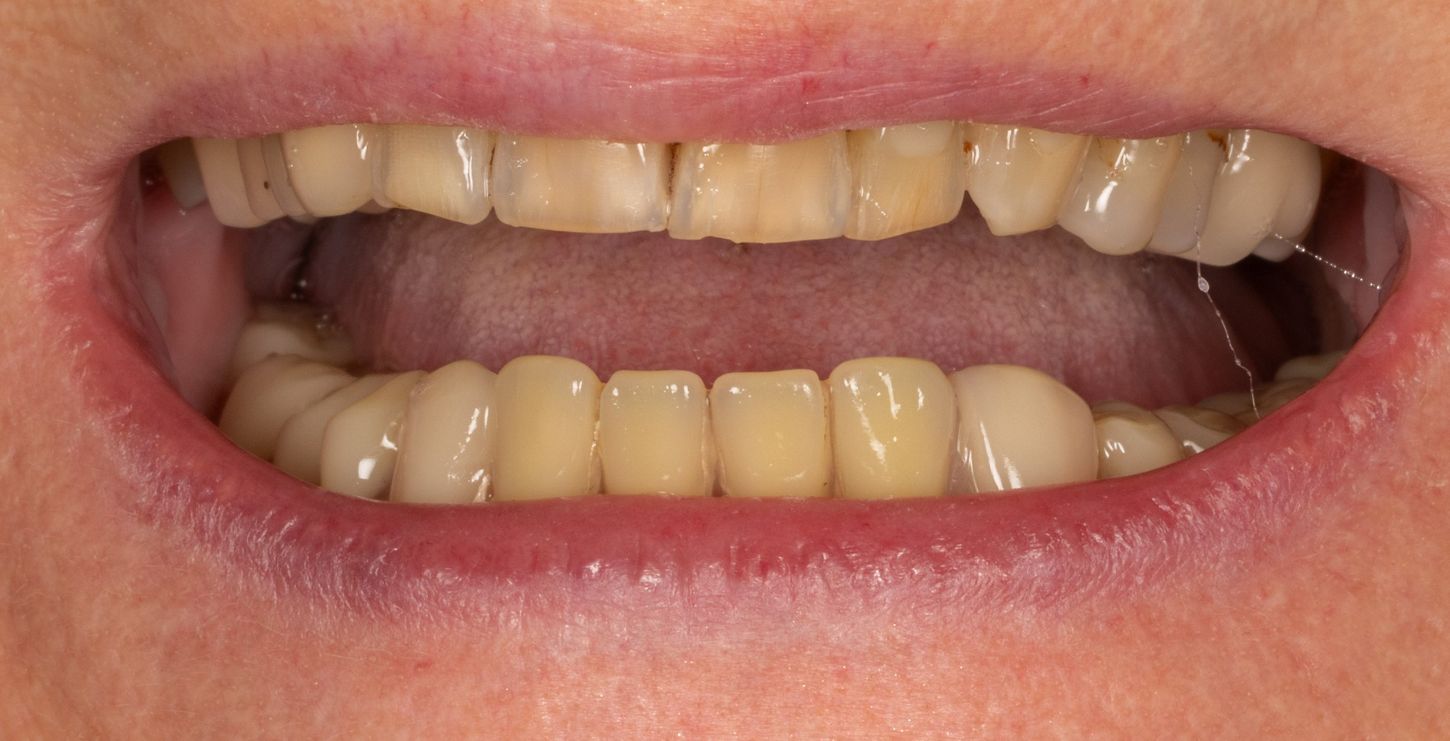

2a. View of the mouth showing limited gingival exposure.

2a

2b. Situation in the maxilla: the periodontal situation is stable.

2b